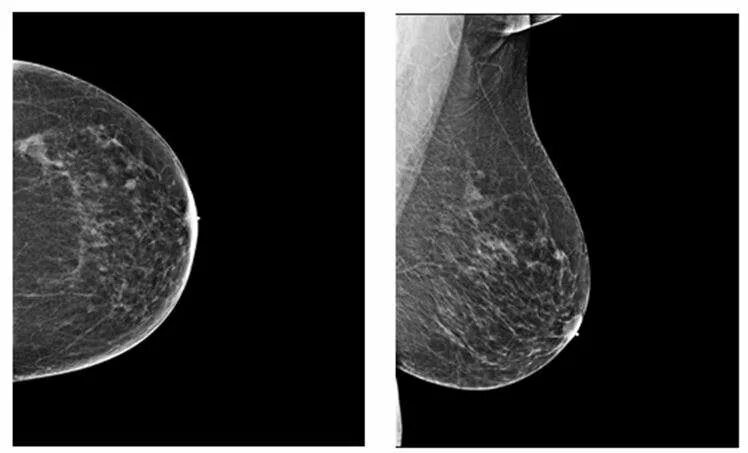

Тип плотности в в молочной железе